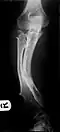

Multiple osteochondromas causing deformity of the forearm (shortening of the radius with secondary bowing of the ulna)